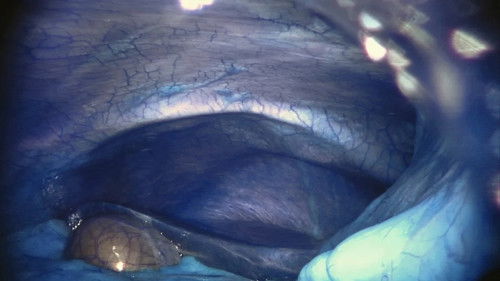

• In an operating theatre in a hospital robotic surgery department, a journey through the human body is undertaken by a specialized robot named Da Vinci. The surgeon conducts the entire operation remotely, controlling the robot’s intricate movements with a joystick.